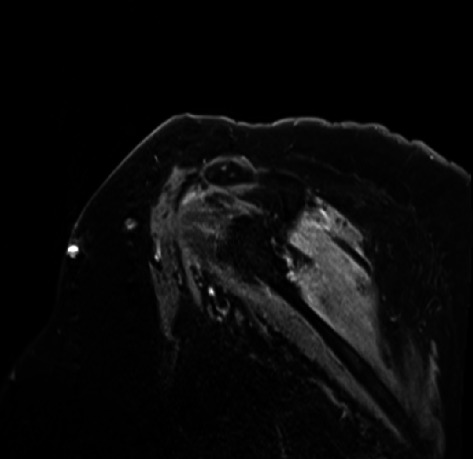

简介:帕森纳-特纳综合征(PTS),也被称为特发性臂丛病,是一种不常见的周围神经病变,双侧PTS的表现更为罕见。嗜血球性淋巴组织细胞增多症(HLH)是一种通常被认为是血液学的高炎症性疾病,但在高达70%的病例中可累及神经系统。病例介绍:56岁白人女性,有SLE、类风湿关节炎、干燥病和桥本甲状腺炎病史,无神经系统病史,因孤立性血小板减少症入院治疗,诊断为HLH,后出现双侧上肢疼痛、无力和麻木。磁共振成像(MRI)显示双侧肩部肌肉轻度对称增强,肌电图/神经传导研究(EMG/NCS)显示双侧肩部肌肉主动失神经支配,支持双侧PTS的诊断。患者开始使用甲基强的松龙1000毫克,连续3天,随后长期逐渐减少类固醇治疗,同时进行物理/职业治疗,症状明显改善。结论:对于新发肩或上臂疼痛、虚弱和感觉缺陷的患者,保持高度的PTS怀疑指数是很重要的,即使发现是双侧的。伴随的炎症性疾病、感染和最近的手术/手术应引起对这种疾病的高度怀疑,并使用相关的诊断方法,如MRI臂丛和肌电图/神经电图,应有助于指导诊断,因为这种情况对治疗非常敏感。

Introduction: Parsonage-Turner syndrome (PTS), also known as idiopathic brachial plexopathy, is an uncommon peripheral neuropathy, and the presentation of bilateral PTS is even rarer. Hemophagocytic lymphohistiocytosis (HLH) is a hyperinflammatory disorder that is normally considered hematologic but can involve the nervous system in up to 70% of cases. Case Presentation: A 56-year-old Caucasian female with a history of SLE, rheumatoid arthritis, Sjogren's disease, and Hashimoto's thyroiditis, but no prior neurologic history, was admitted for the management of isolated thrombocytopenia, diagnosed with HLH, and then developed bilateral upper extremity pain, weakness, and numbness. A diagnosis of bilateral PTS was supported by magnetic resonance imaging (MRI) findings of mild symmetric increased enhancement in the bilateral shoulder muscles, and electromyography/nerve conduction study (EMG/NCS) revealed active denervation in the shoulder muscles bilaterally. The patient was started on methylprednisolone 1000 mg for three days, followed by a long steroid taper along with physical/occupational therapy with significant improvement of her symptoms. Conclusion: It is important to maintain a high index of suspicion for PTS in patients with new-onset shoulder or upper arm pain, weakness, and sensory deficits, even if findings are bilateral. Concomitant inflammatory disorders, infection, and recent surgeries/procedures should prompt a high degree of suspicion of this disorder, and the use of relevant diagnostics, such as MRI brachial plexus and EMG/NCS, should help guide diagnosis, as this condition is very responsive to treatment.